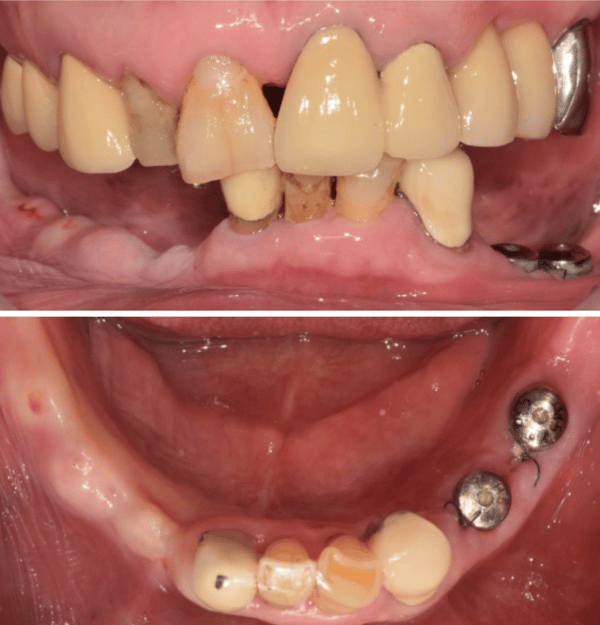

手術現場:不翻瓣與立即受力的精準演繹

手術當天,數位規劃的價值轉化為實質的臨床紅利。由於術前已透過軟體精確計算了植體位置與角度,Dr. Lee 得以執行不翻瓣手術。手術導板與牙齦的密合度極佳,無需額外的骨釘固定,手術過程安靜、快速且出血量極低。這對於病患來說,不再是一場血淋淋的手術,而是一次精密的醫療體驗。

更令人驚艷的是立即受力的環節。利用術前設計好的檔案,醫師在手術當天就為病患裝戴上了臨時贋復物。這裡有一個值得注意的細節:Dr. Lee 並沒有急著製作最終假牙,而是先利用客製化的鈦金屬基台搭配 PMMA 臨時牙冠。

這並非多此一舉,而是為了在軟組織癒合期,透過客製化基台塑形出完美的穿透輪廓,同時利用這段時間重新建立並確認病患的咬合關係。這種「以時間換取空間」的策略,只有在數位流程能夠快速、低成本地製作臨時贋復物的前提下才得以實現。

經過兩個月的癒合期,從 X 光片中可以清晰看見,即便經歷了立即受力,植體周圍的邊緣骨依然穩定,毫無吸收跡象。這證明了數位導引手術在分散咬合力上的卓越表現。最終,醫師利用已經確認穩定的咬合記錄,透過數位印模製作了全鋯冠。當最終贋復物裝在病患口中,那種絲毫不差的密合度與無需反覆修磨的順暢感,正是數位全口重建最迷人的終點。